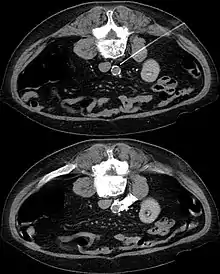

Sympathectomy under CT guidance. The patient lies on his stomach. In the first picture the injection needle is visible with its tip behind the aorta. The second image shows the distribution contrast with lysis bolus.

The sympathetic plexus can also be blocked in other parts of the body. Lying on the major abdominal vessels sympathetic plexus may, for example, under local anesthesia guided by a CT scan it can be turned off by injection of concentrated alcohol (interventional radiology).

In CT guided lumbar sympathicolysis, the site of neurolytic solution injection is chosen at the level of L2-L3 vertebra level. The needle should avoid the vertebral transverse process, ureter, pelvicalyceal system, and other major blood vessels. The target injection site would be anteromedial to the psoas muscle and dorsolateral to the abdominal aorta, where the sympathetic trunk would most likely be located.[1]

After the skin of the puncture site is cleaned, 2% lignocaine is injected into the to numb the skin and also the needle trajectory. Then a 22G China needle is inserted into the target site, which is bounded by the vertebral body, aorta, inferior vena cava, and psoas muscle. This region houses the lumbar sympathetic ganglion. Then, iodinated contrast medium (iohexol) and lignociane is injected into the target site to check the position of the needle tip. Once the needle tip position is confirmed, a mixture of neurolytic solution (99.9% alcohol) and iodinated contrast medium (at a ratio of 10:1) is injected into the target site.[1]